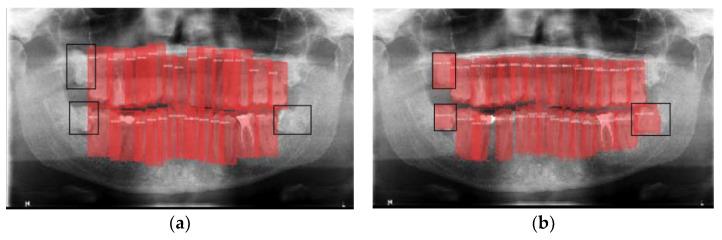

一种采用卷积神经网络对牙齿有无进行影像学检测的验证方法。

A Validation Employing Convolutional Neural Network for the Radiographic Detection of Absence or Presence of Teeth.

Dental radiography plays an important role in clinical diagnosis, treatment and making decisions. In recent years, efforts have been made on developing techniques to detect objects in images. The aim of this study was to detect the absence or presence of teeth using an effective convolutional neural network, which reduces calculation times and has success rates greater than 95%. A total of 8000 dental panoramic images were collected. Each image and each tooth was categorized, independently and manually, by two experts with more than three years of experience in general dentistry. The neural network used consists of two main layers: object detection and classification, which is the support of the previous one. A Matterport Mask RCNN was employed in the object detection. A ResNet (Atrous Convolution) was employed in the classification layer. The neural model achieved a total loss of 0.76% (accuracy of 99.24%). The architecture used in the present study returned an almost perfect accuracy in detecting teeth on images from different devices and different pathologies and ages.

摘要

口腔放射成像在临床诊断、治疗及决策过程中发挥着重要作用。近年来,人们致力于开发图像中物体检测技术。本研究的目的是使用一种有效的卷积神经网络来检测牙齿的有无,该网络可减少计算时间且成功率大于95%。共收集了8000张口腔全景图像。由两位具有三年以上普通牙科经验的专家对每张图像及每颗牙齿进行独立且手动的分类。所使用的神经网络由两个主要层组成:目标检测层和分类层,分类层以前者为支撑。目标检测采用了Matterport Mask RCNN。分类层采用了ResNet(空洞卷积)。该神经模型的总损失率为0.76%(准确率为99.24%)。本研究中使用的架构在检测来自不同设备、不同病理情况及不同年龄的图像中的牙齿时,返回了几乎完美的准确率。